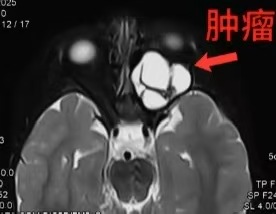

眼眶影像图(箭头所指白色为肿瘤)

影像学显示,肿瘤在幼小眼眶内“野蛮”生长,充满整个眶腔,严重挤压眼球和视神经,分离过程中稍微刺激或者压迫,就可能导致永久失明。更危险的是,肿瘤已撑开眶上裂,随时可能钻进颅内;同时撑开了眶下裂、翼腭窝,挤进颞下窝和面深部。最关键的是,翼突受压变形,与颌内动脉紧贴一起。这根动脉一旦破裂,将引起大出血,可迅速导致患儿失血性休克。